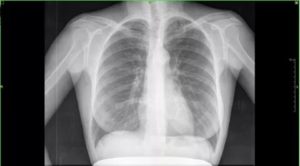

Рентгеновский снимок здоровых легких фото